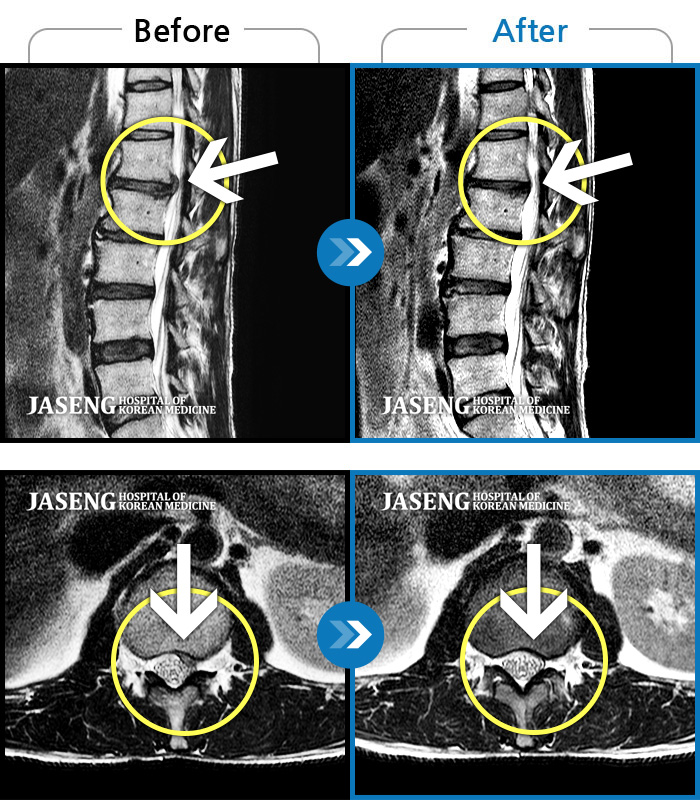

Before

After

허리 통증 및 우측 골반 저림이 심하여 일상생활이 불편한 상태였습니다.

2023.10.12 ~ 2025.11.21